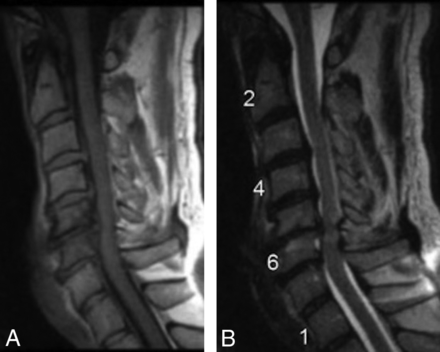

A 59-year-old male patient with neck pain who underwent discectomy at C5–C6 and was biopsy-positive for P acnes. Preoperative sagittal MR imaging (T1- and T2-weighted) shows MC1 and evidence of myelopathy at C5–C6.